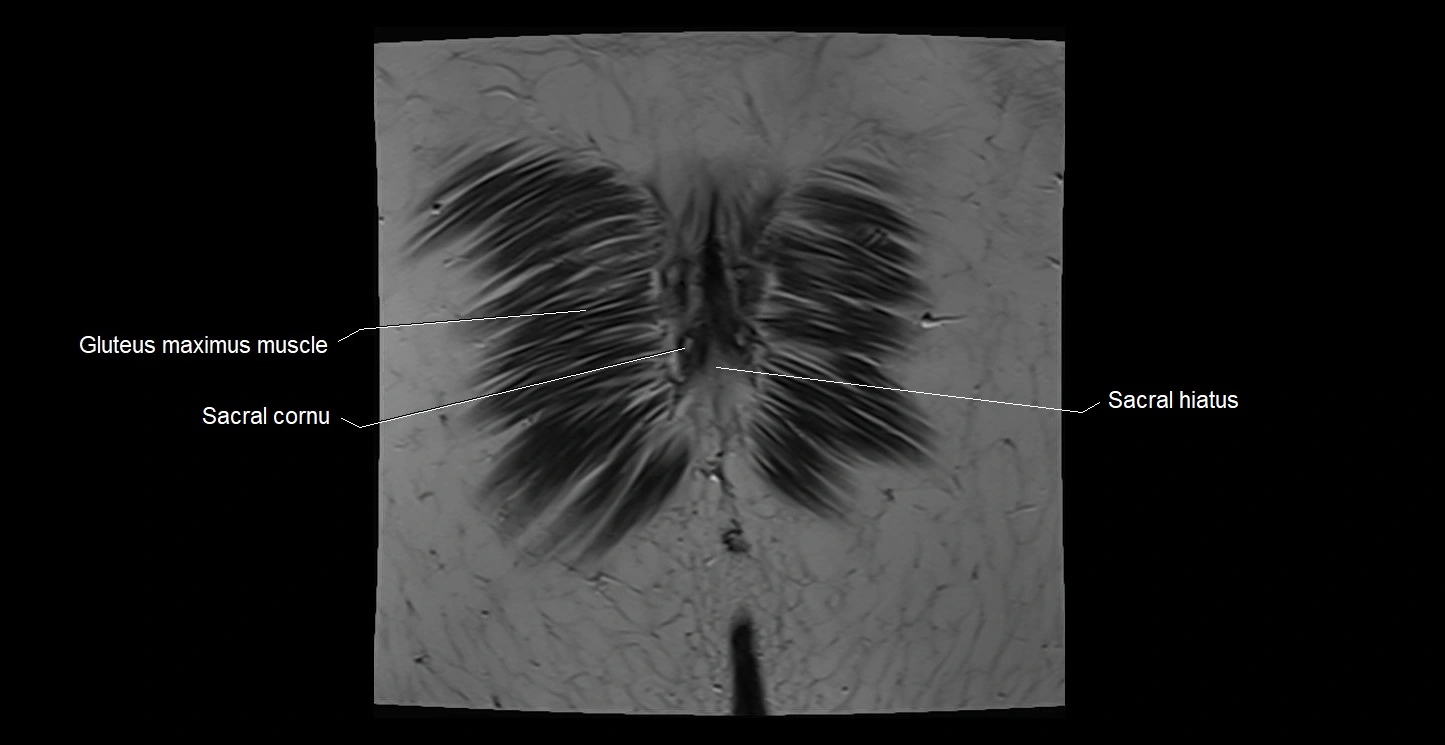

- Gluteus maximus muscle

- Sacral cornu (sacral horn)

- Sacral hiatus